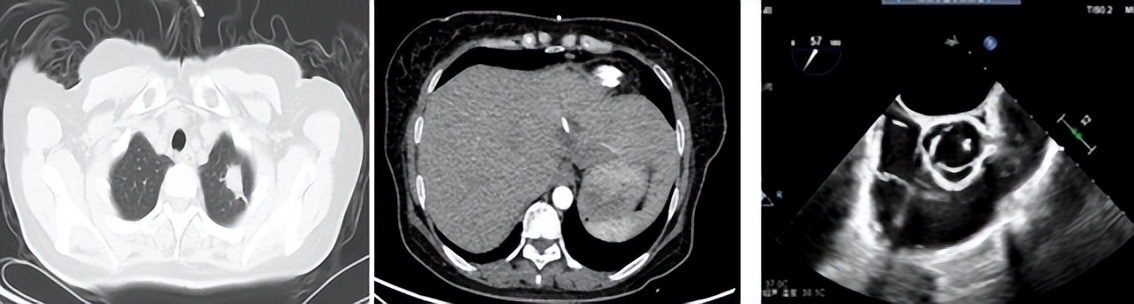

通过转诊绿色通道,患者被第一时间转入我院本部呼吸与危重医学一科。入院后复查影像:胸部左肺团块、斑片灶,考虑肺脓肿;肝左叶团状蜂窝,考虑肝脓肿;心脏超声示主动脉瓣赘生物。

医生立即进行病情分析:患者因长期未能有效控糖,导致身体免疫力低下,而营养丰富的血液却成了细菌培养基,起初一点点的感染逐步加重至严重感染,肝脏内形成接近一个拳头大小的脓腔,肺部病灶均位于胸膜下考虑血源性感染,疑惑的是左上肺病灶呈现“鬼脸征”,同时还伴有感染性心内膜炎及瓣膜赘生物形成。

有了病原学和药敏的支持,医院立即调整抗生素方案并充分引流,规范管理血糖,患者体温很快降至正常,各项生命体征及指标达临床稳定;仅1周的时间患者肺部病灶、肝脓肿及心脏瓣膜赘生物均明显缩小;引流1月后复查肝脓肿明显缩小,引流液消失,拔除引流管,顺利出院。